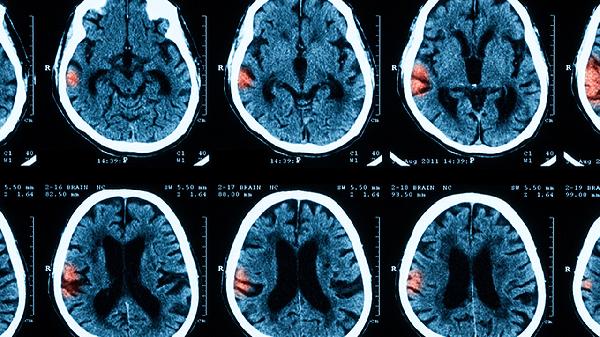

孩子脑膜炎有哪些表现和诱因

小儿脑膜炎的典型表现包括发烧、头痛和呕吐,这些症状可能由病毒感染、细菌感染、真菌感染、寄生虫感染或免疫系统异常等多种因素引起。